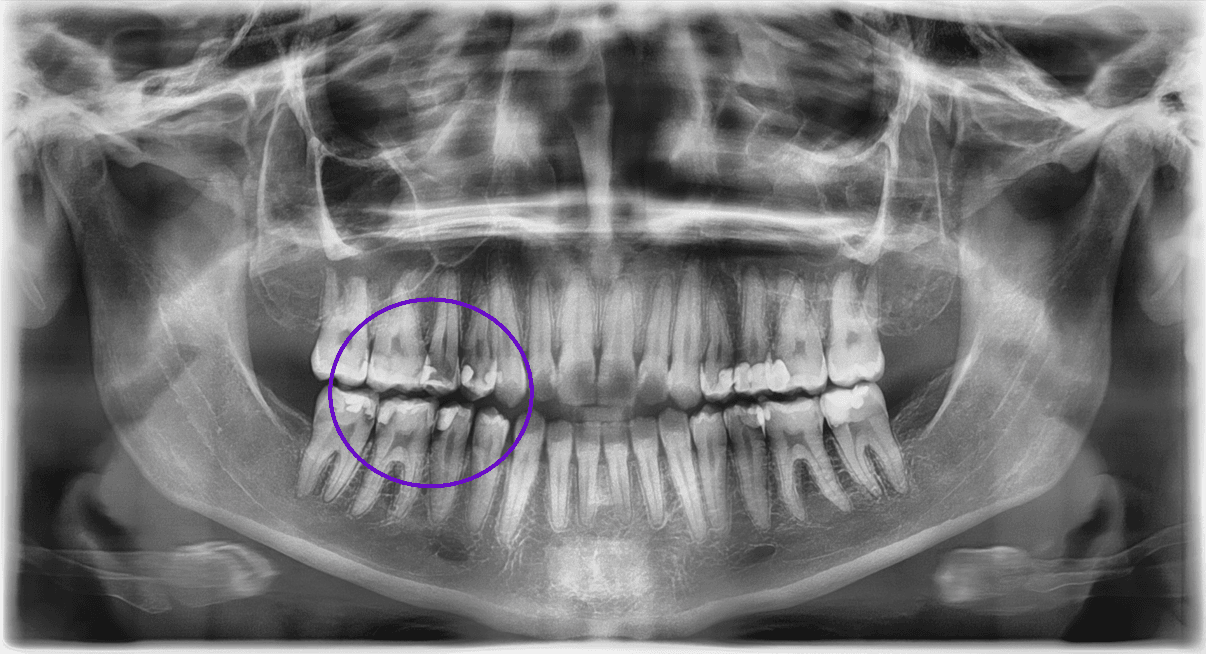

Achados radiográficos radilúcidos:

Achados radiolúcidos em radiografias podem ser indicativos de várias condições que afetam a saúde bucal e precisam ser considerados e avaliados antes de realizar movimentações ortodônticas. Alguns achados mais comuns são:

Cáries: Devem ser tratadas antes do início do tratamento ortodôntico, para evitar complicações, uma vez que a progressão da cárie pode afetar a estrutura dentária e saúde periodontal.

Lesões periapicais: Devem ser tratadas adequadamente com endodontia antes do início da ortodontia e acompanhamento radiográfico.

Cistos: A presença de cistos pode interferir os movimento ortodônticos e a saúde bucal em geral. O tratamento ortodôntico pode ser contraindicado até que a condição seja resolvida, geralmente com cirurgia ou outros tratamentos médicos.